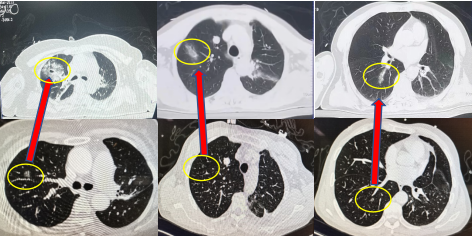

近日,吉大一院胸外一科主任刘伟团队在中山大学附属肿瘤医院教授罗孔嘉的指导下,在呼吸科教授谷月、麻醉科教授苑野、放射线科教授曹殿波、第一手术室护士长于婧及护士的密切配合下,在第一手术室杂交手术间成功为2位患者、3处磨玻璃结节完成微波消融治疗。此次消融在电磁导航支气管镜(Electromagnetic+Navigation+Bronchoscopy%2C+ENB)引导下,精准定位、准确消融,术中CT复核一站式完成。此次肺结节消融的成功完成标志着吉大一院在肺部结节微创治疗方面达到国内领先水平。efU帝国网站管理系统

电磁导航定位技术的到来为肺结节患者带来了全新的治疗体验,气管镜在磁导航的引导下可达到“全肺范围”,该技术经人体自然腔道,超微创,可对肺内微小结节进行精准定位。随后进行微波消融(MWA)治疗,其原理是肿瘤组织内的水分子、蛋白质分子等极性分子在微波电磁场的作用下产生极高速振动,造成分子之间的相互碰撞、相互摩擦,在短时间内产生高达60℃-150℃的高温,从而导致细胞凝固性坏死。

吉大一院第一手术室杂交手术间配有术中CT,可对治疗结果进行立刻复核,保障术中治疗的准确性与安全性。